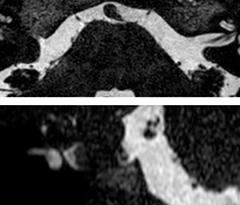

Fast acute stroke protocol

This is an example of acute ischemic stroke with distal occlusion of the right posterior cerebral artery. Note the improved visibility of the ischemic territory on the diffusion weighted image with high b-value. The 3D FLAIR shows a distal PCA occlusion. The fast SWIp depicts the thrombus on the isolated second echo image. The total scan time (including SmartBrain, preparations and a fast 3D T1w TSE Gd) is 8:00 minutes.